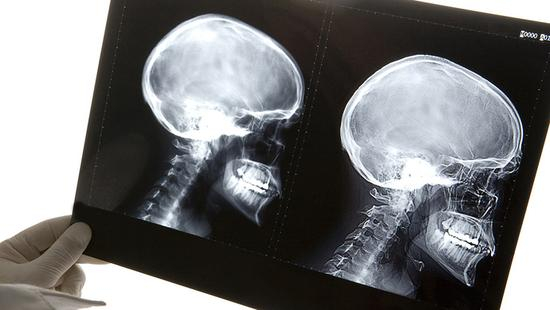

据英国《每日邮报》17日报道,意大利都灵高级神经调节小组的神经外科专家塞尔吉·卡纳瓦罗(Sergio Canavero)宣布,世界首例人类头部移植手术近日已被他在一具遗体上成功实施,手术在中国哈尔滨医科大学进行,历时18小时,任晓平教授参与指导了该手术。专家小组在奥利地首都维也纳的新闻发布会上表示,目前他们可能已经成功找到了头颅移植手术中重新连接脊椎、神经、血管的方式,他们很快将在申请参加试验的患者身上进行类似手术尝试。

消息一出,引发全球轩然大波。解放日报·上观新闻记者就此采访上海交通大学医学院附属瑞金医院神经外科主任卞留贯,他表示,从技术层面来看,头部移植手术为复合组织移植手术,复杂程度非同一般,“相比肢体移植手术,脑组织对缺血的耐受性更差,同时对中枢神经系统的连接有极大挑战,脊髓缝合更是难上加难。此外,术后还需要注射大量免疫抑制剂,防止免疫排斥反应等。”

世界神经外科联合会(WFNS)就此事件发表严肃声明。 来源:世界神经外科联合会(WFNS)官网

上海交通大学医学院附属仁济医院神经外科主任张晓华则直言,“两位教授至今还没有对医学界关注的关键问题给出任何具有说服力的证据:中枢神经如何再生?手术过程中如何进行脑保护?”对此,任晓平在接受媒体采访时说,接下来的一周时间里,有关本次头移植的相关数据、过程和结果将在美国学术杂志上发表,且表示“既然学术杂志会刊发论文,就证明手术做得有学术价值。”

“对于这一结果,我们拭目以待。”神经外科学界的诸多专家对此保持观望态度,然而作为全球最大的神经外科学术组织,世界神经外科联合会(WFNS)却为此发表了严肃声明,其中明确指出,施行头颅移植的技术具有一定可能性,但目前,只是能在人体头颈必需的脑血管吻合基础上建立脑血液循环,由于脊髓横断后,头与身体不能建立神经联系,人们仍没有能力做脊髓离断后的神经原再生。“因此,头颅移植不但在伦理学上不可接受,在科学方面也毫无意义。”

“不可接受、毫无意义”8个字是否已为这一事件盖棺定论?卞留贯则有更为乐观的看法,“2013年,任晓平在哈医大进行了首次老鼠脑部移植实验,并由此计划在灵长类动物身上进一步实验。同时既往认为中枢神经一旦被切断将不会生长、功能得不到恢复,但目前学界研究发现,使用聚乙二醇冲洗脊髓融合的区域后,通过GEMINI脊髓融合技术可让两端脊髓有效融合在一起。或许随着科学的发展,头部移植在可期的未来能真正实现。”

针对大众更为关心的伦理问题,张晓华同样表达了疑惑。“人是独立存在的个体,头部移植后,具体归回到哪个角色?捐献者还是受捐者?不过目前,这台手术只在遗体上进行操作,还属于解剖学范畴,对于医学伦理的讨论还为时尚早。”